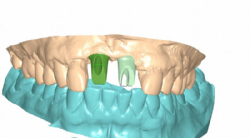

Die einartikulierten und mit Zahnfleischmaske versehenen Modelle wurden in das Atlantis®-Labor geschickt. Nachdem dort die Modelle eingescannt worden waren, konnte das Design der Atlantis®-Abutments in enger Absprache mit Zahnarzt und Zahntechniker-Meister geplant werden. Die Kommunikation geschieht virtuell mittels Atlantis VAD® Software.

Abbildung 5: Virtuelles Bild der Atlantis®-Abutments in der Planungsphase

Obwohl der Patient in Bezug auf seine ästhetischen Wünsche nicht sehr anspruchsvoll war, wurde dennoch entschieden, Zirkondioxid-Abutments zu verwenden. Gerade in ästhetisch relevanten Zonen wie den oberen Schneidezähnen erlauben diese ein wesentlich anspruchsvolleres Ergebnis. Neben den Zirkondioxid-Abutments könnten im Atlantis®-System auch Titan-Abutments und goldfärbige titannitrid-beschichtete Abutments verwendet werden.

Die nach der Planung im Atlantis®-Labor gefertigten Abutments standen nach wenigen Tagen zur Verfügung.